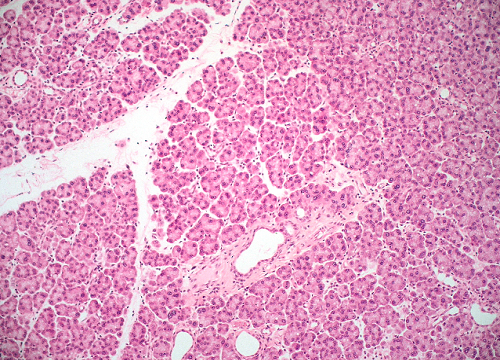

Question 8

Question

Label this image

Image:

f15e04b7-e7fd-4d7d-a896-1a0ab97f8092 (image/png)

Answer

Parotid Gland